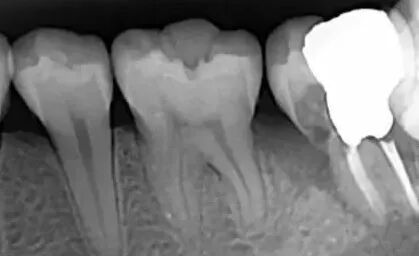

局部牙片:一般能拍到三颗牙齿,医生要观察单颗牙齿时会用到这种牙片,此时拍摄小牙片会比全景片来得清楚。

常见的蛀牙通常可以通过牙片发现,尤其是龋坏比较多的,在牙片上会出现黑色阴影的缺损。但如果是邻面龋,就需要到口腔机构,让医师用探针、口镜等进行检查确定。

种植牙等修复体在口腔全景片上展现的通常是白色的,可以很清晰的看出来。另外补牙材料和金属或者全瓷牙冠也会显示出亮白色。